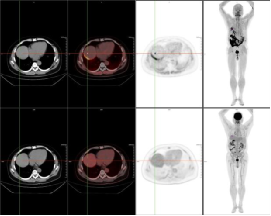

例一:患者53岁男性,肝内胆管癌术后7月余,八周期化疗后复查。图像第一排为FAPI显像;第二排为FDG显像。

肝顶部及残肝右叶病灶FDG显像未见明显显示,而FAPI显像明显显示,CT密度均未见明显异常。

且较本院增强MR及FDG显像新发现肝左叶病灶;右肺门淋巴结FDG显像及FAPI显像均代谢增高,高度怀疑转移灶。